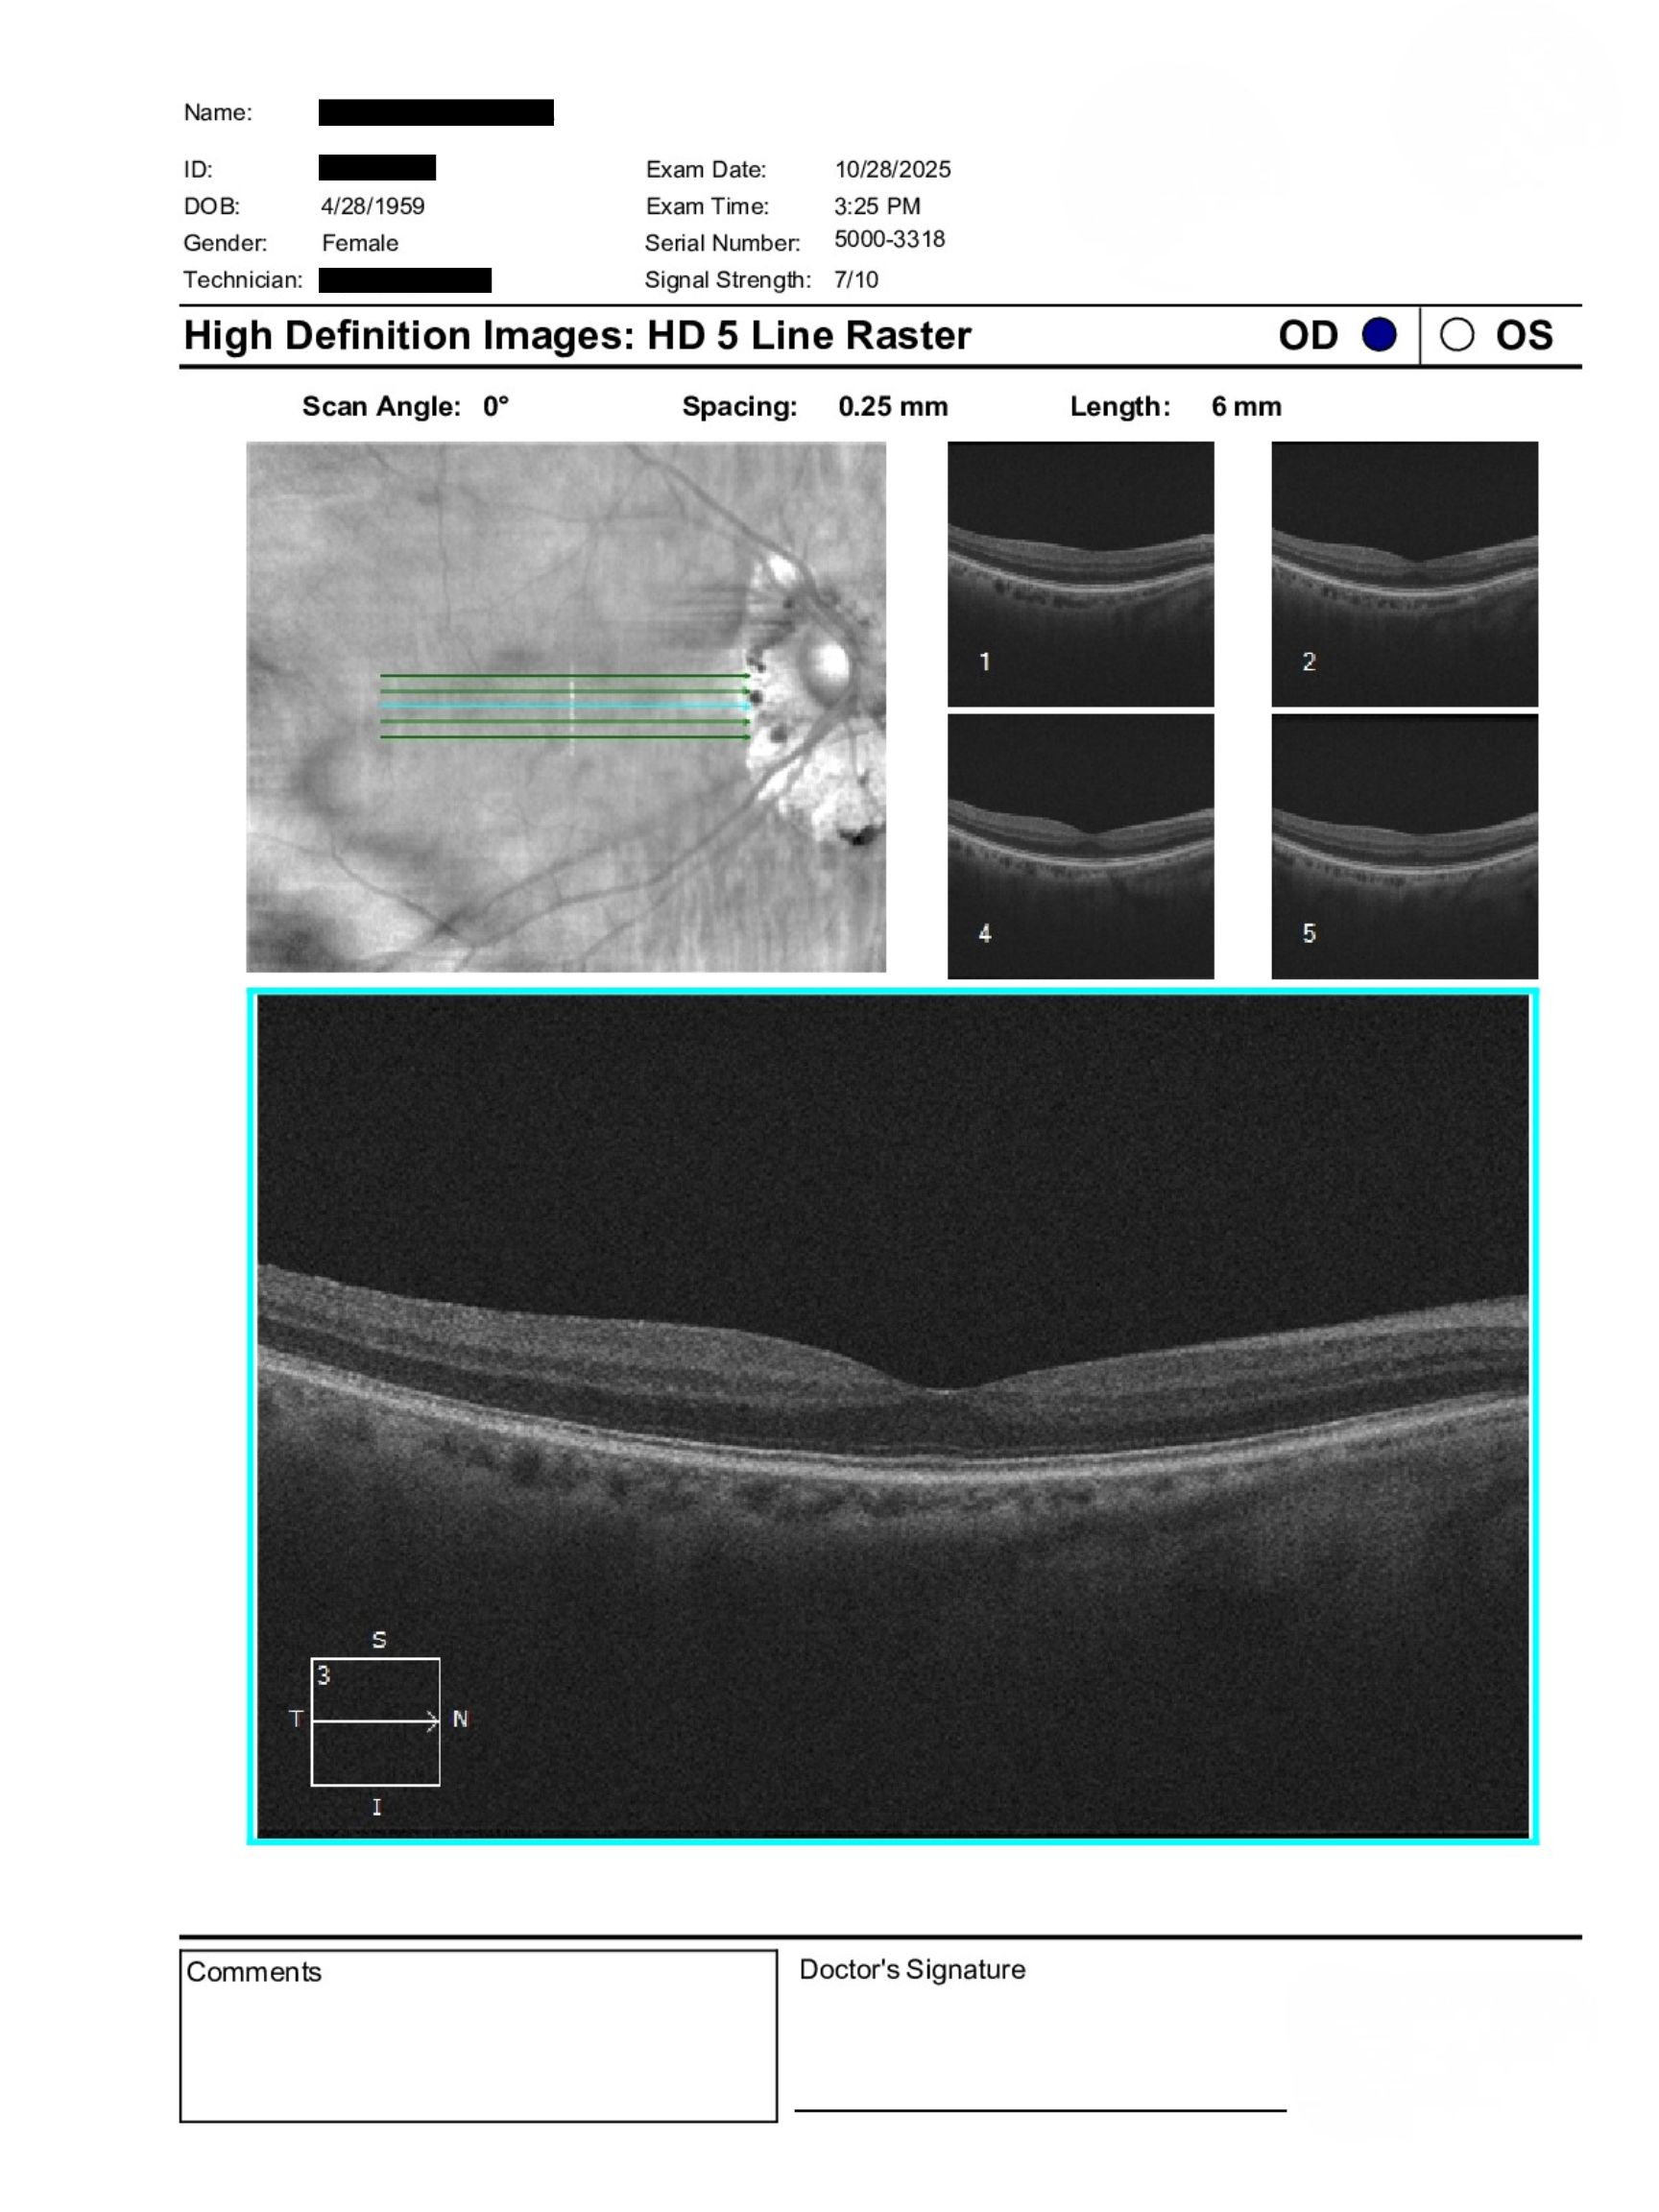

Case Study: Unilateral Macular PED With Edema

66-year-old with unilateral macular PED and reduced vision OS on a background of peripheral retinal changes. Explore evaluation and referral urgency.

A 66-year-old patient was referred for evaluation of a left eye macular concern identified prior to travel. BCVA was 6/15+1 OD and 6/24-1 OS, with IOPs of 13 mmHg OU. Anterior segment exam showed bilateral nuclear sclerotic and posterior subcapsular cataracts. Posterior segment findings included a large PED OS and 360-degree peripheral RPE changes OU.

The clinical picture raises concern for an inflammatory or infectious chorioretinal process with secondary neovascular complications. Differentiating between similar-appearing peripheral retinal conditions is important, particularly when macular involvement is present.

The presence of a pigment epithelial detachment with associated edema warrants urgent in-person retinal evaluation to assess for possible neovascular activity. Early identification and timely intervention are critical to preserving visual function. Coordinated care between optometry and retina specialists allows for appropriate triage and expedited management when high-risk features are identified.

Peripheral chorioretinal syndromes can present with characteristic fundus findings and may be associated with secondary macular complications such as pigment epithelial detachments or neovascularization. Multimodal imaging, including OCT and angiography, plays a key role in distinguishing between inflammatory and infectious etiologies. Early detection of macular involvement is essential for preventing vision loss.